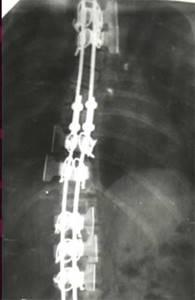

| Результат коррекции сколиотической деформации эндокорректором с деротационными скобами |

| Больной П-ко, 15 лет Поясничный сколиоз III степени |

Результат оперативного лечения |